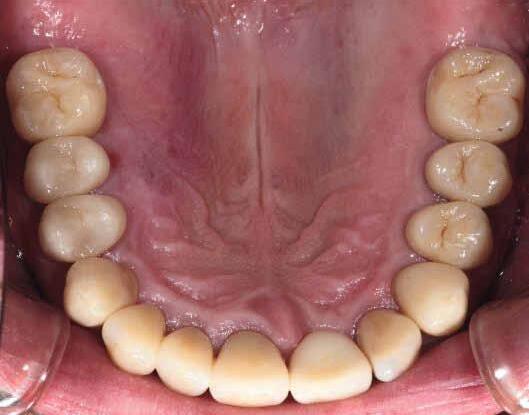

This case was performed by Dr Homa Zadeh, DDS, PhD, a respected leader in periodontology and implant dentistry. Dr Zadeh’s approach emphasizes biologically driven protocols and evidence-based techniques, making this case a strong example of clinical excellence using the Tapered Pro Conical system. It involves the replacement of two front anterior teeth after they fractured off and the full restoration process.

Fig 1. Patient anterior situation. Two anterior crowns fractured off.

Fig 2. Intraoral radiograph indicating tooth structural loss extent.

Fig 3. Provisional restorations on central incisors and gingival images. The gingival contours were optimal, and the gingival phenotype was thick.

Fig 4. Alveolar bone imaging. The alveolar bone was intact, and the alveolar crest was approximately 4mm apical to the restorative margin.

Fig 5. Central incisors extracted using minimally invasive protocol. Alveolar bone and gingival tissues were intact after extraction

Fig 6. BioHorizons Tapered Pro Conical implants of 3.8 x 15mm placed according to the plan.

Fig 7. Implants immediately after installation.

Fig 8. Scanbody installation for custom abutment and definite restoration fabrication.

Fig 9. Periapical radiograph for verification of proper seating of the scanbodies.

Fig 11. Bone graft filling the horizontal gap between socket and implants.

Fig 12. Screw-retained provisional restoration placed into implants, with LPRF placed to protect graft material.

Fig 13. Radiograph of implants, grafts and Provisionals.

Fig 14. Clinical view at two days post-operative visit.

Fig 15. Clinical view at two days post-operative visit

Fig 16. Patient’s smile after implantation and previsualization